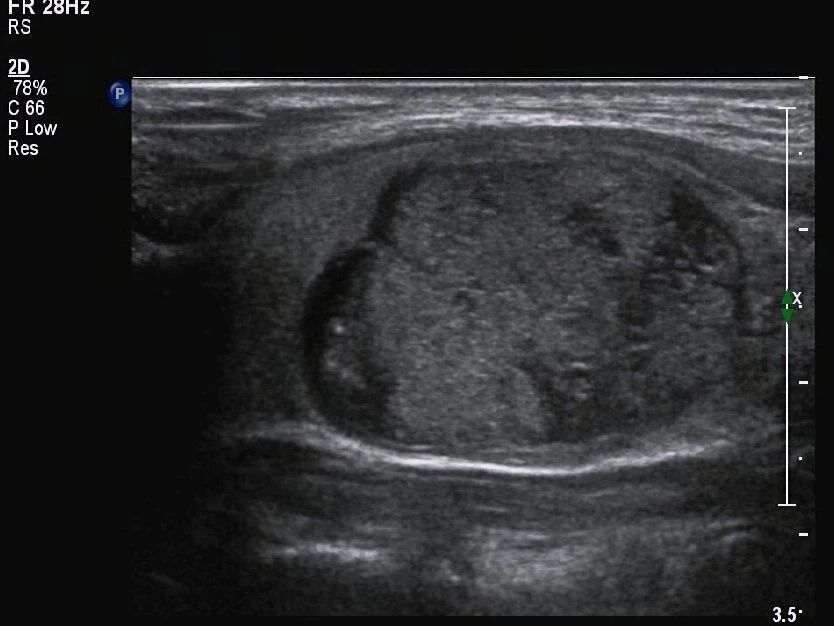

囊实性结节,存在包含液态的囊性部分,还存有含有固态的实性部分,这种具备混合结构的状况,给诊断带来特殊挑战,要留意的关键在于,其与由大量微小囊腔构成、基本没有实性成分的海绵状结节有着本质差别 。

在考量恶性风险时,结节全然呈现囊性状态,结节全然呈现海绵状模样,一般而言这种结节偏向良性,作为实性的结节,其风险相对较高,然而囊实性结节所具备的风险,处于这两者的范围区间之内,临床所获取的数据表明,囊实性结节致使恶变的概率,显著比完全呈现为实性样子的结节来得低。

声晕特征的分析价值

声晕特征在结节周围存在着,可为诊断提供重要线索。薄且均匀的声晕存在着,肿瘤一般是良性的,代表结节生长不迅速,对周围其他组织施加正常均匀压迫形成这种情况。这种声晕,在甲状腺结肠里颇为常见。

一些结节属于恶性,它的声晕呈现特定特点,这些声晕特征并非单一统一,有的声晕完全不存在,呈现为空环状,有的厚,然而声墙的厚度不均匀,这种声晕不均匀的情况,恰恰是浸润恶性生长的趋势所造成的特性,是判断结节为良性或恶行类型的重要参考指标之一的体现,而这一点同样能够用作判断依据来加以确诊恶性。